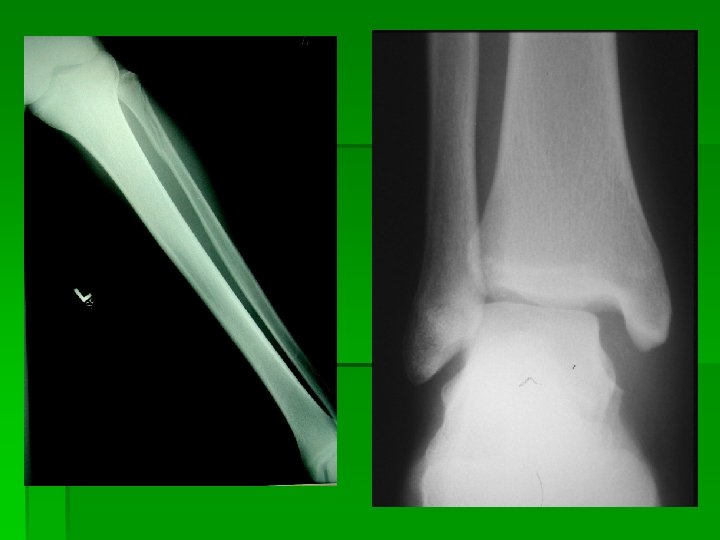

The syndesmosis ligament is often also injured with an eversion force. If the tibia and fibula spread on the talus, the ankle mortise is disrupted and the ankle can become very unstable. It is also not unusual to see an associated fibula fracture with an eversion mechanism. (see x-rays below) Assessment of a syndesmosis sprain will be difficult for the initial 24 to 48 hours. If the ankle is quite swollen and edematous assessment of a syndesmosis sprain may be difficult until the pain and swelling have isolated to individual areas or x-rays show some spreading of the ankle mortise.

Maison - Neuve type fracture.

Distal Fibula fracture with associated medial deltoid ligament disruption. This injury is frequently the result of the foot being planted with a valgus load applied to the leg.

Notice the disruption of the medial deltoid ligament and the widening between the medial malleolus and the talus. This is indicative of a ruptured deltoid ligament.